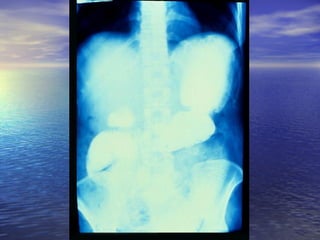

5.- FÍSTULAS: Enf. De Crohn, tumores5.- FÍSTULAS: Enf. De Crohn, tumores

malignos y postoperatoriosmalignos y postoperatorios

6.- ANORMALIDADES EXTRÍNSECAS:6.- ANORMALIDADES EXTRÍNSECAS:

Metástasis , serosa, ascitis, lesionesMetástasis , serosa, ascitis, lesiones

inflamatorias o neoplasias cercanas.inflamatorias o neoplasias cercanas.

7.- DILUCIÓN DEL MEDIO DE7.- DILUCIÓN DEL MEDIO DE

CONTRASTE: Lesiones proximales uCONTRASTE: Lesiones proximales u

obstructivas, Sx. De Zollinger Ellison.obstructivas, Sx. De Zollinger Ellison.